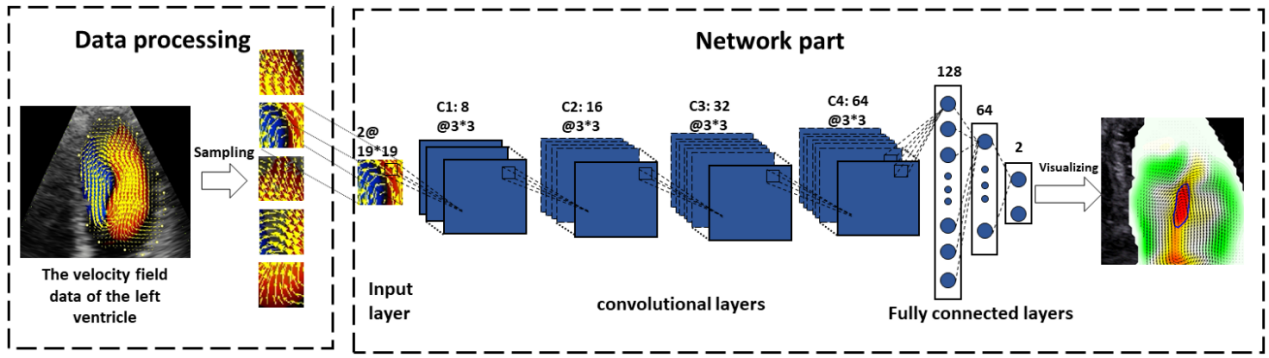

基于超声技术采集心腔内的血流速度,采用自动分割方法对左心房的漩涡进行识别。我们以CNN网络为基础,创新性设计了一种专门用于识别心腔内漩涡的IVD-CNN网络(如图7所示)。

图7 所提出的漩涡识别网络体系结构